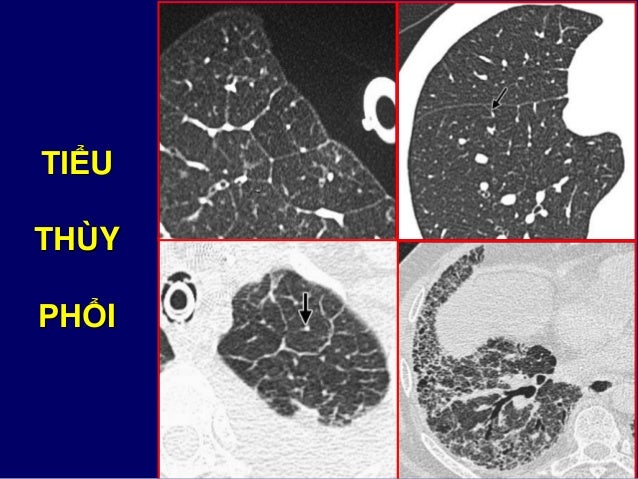

6. 6. Hít không đủ sâu  Mờ vùng đáy giả tạo Hít lại cho đủ sâu  Biến mất vùng mờ ở đáy

7. 7. Cung sườn 9 sau Cung sườn 6 trước Nằm trên cơ hoành 1 2 3 4 5 6 7 8 9 1 2 3 4 5 6

29. 29. TIỂU THÙY PHỔI

30. 30. TIỂU THÙY PHỔI